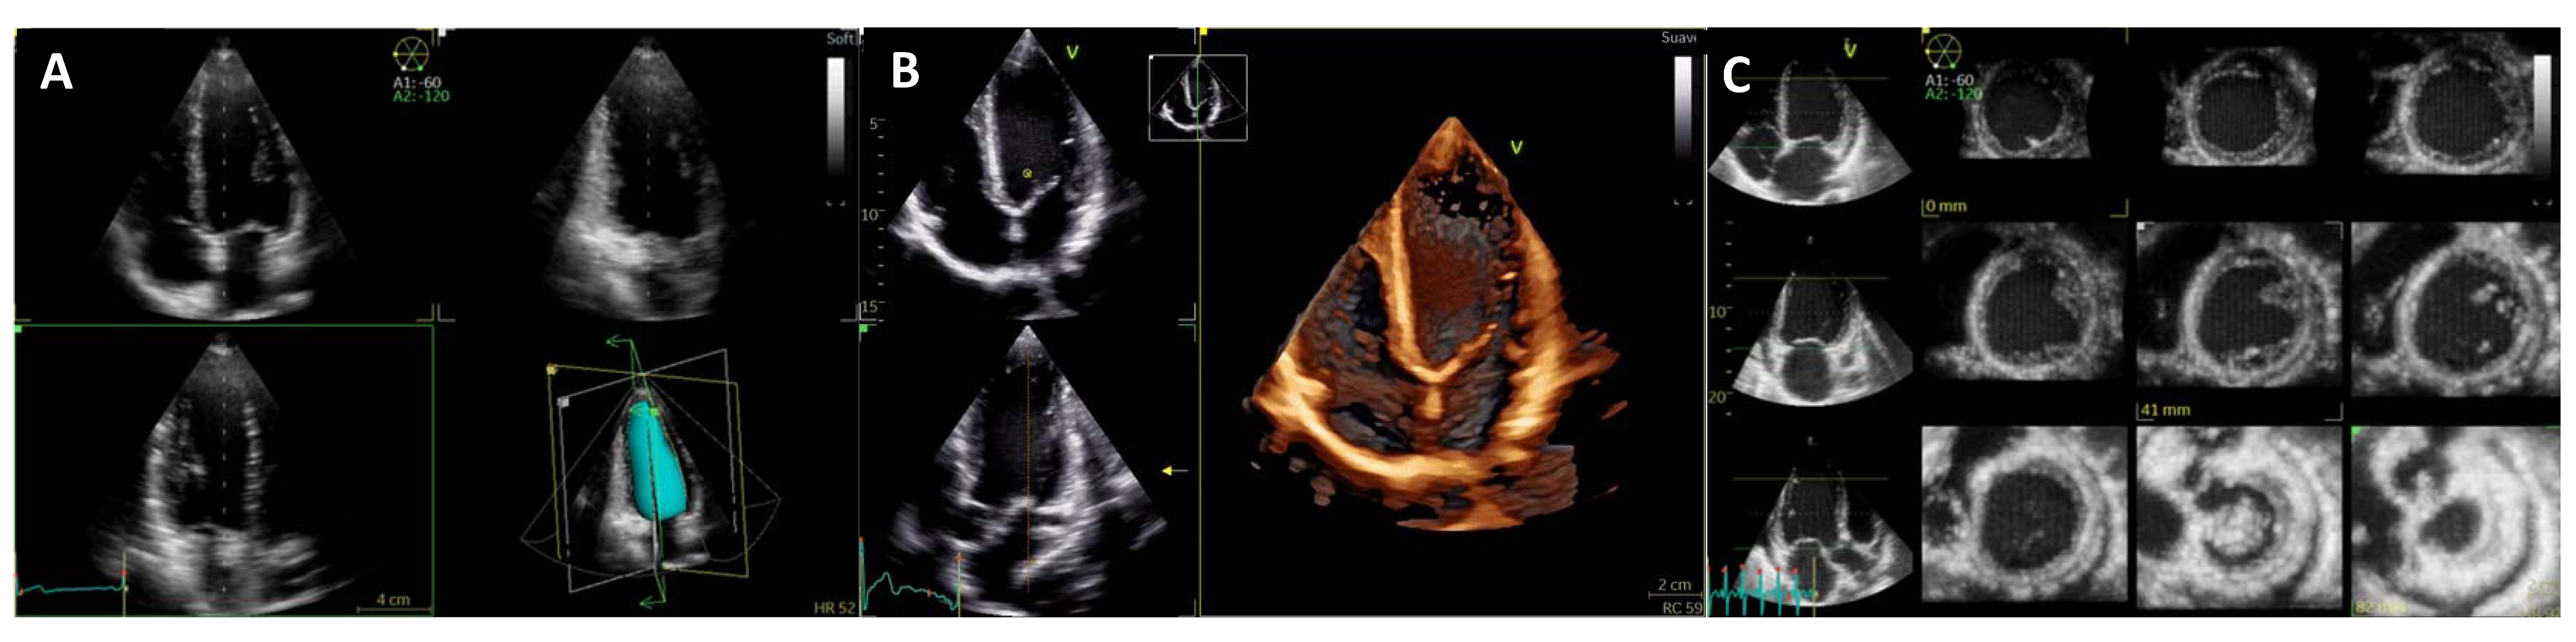

3. Dilated Cardiomyopathy